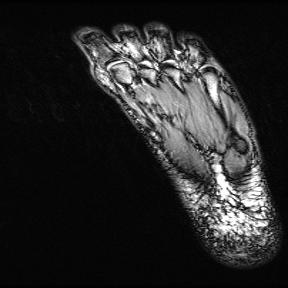

Test data: For evaluation, we used the ten 352352 MRI images in Fig. 2, which were not in the training dataset. The measurements were constructed using (1) with complex AWGN whose variance was adjusted to give a pre-masking SNR of 40 dB. For the multicoil experiments, we used coil sensitivities simulated using the Biot-Savart law, while in the single-coil case, we used .